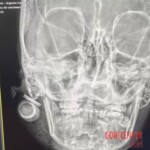

Although a rubber bullet is a non-lethal weapon, at such close range it can cause very serious injury. The projectile lodged in her head, causing a fractured jaw.

Doctors say the injury could have caused irreversible damage to the woman’s hearing, speech and even her eyesight. She is currently unable to open her mouth or close her jaw.